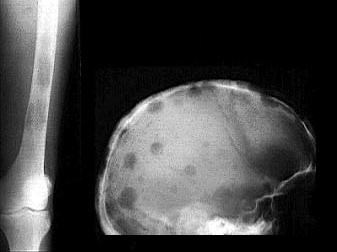

56. A csontok daganatos megbetegedései

A csonttumorok éjszaka fokozódó, állandó fájdalmat idéznek elő.

Patológiás törés gyakran előfordulhat.

A diagnózis gyanuját az általános klinikai tünetek, a gyorsult süllyedés, valamint a radiológiai elváltozások alapozzák meg.